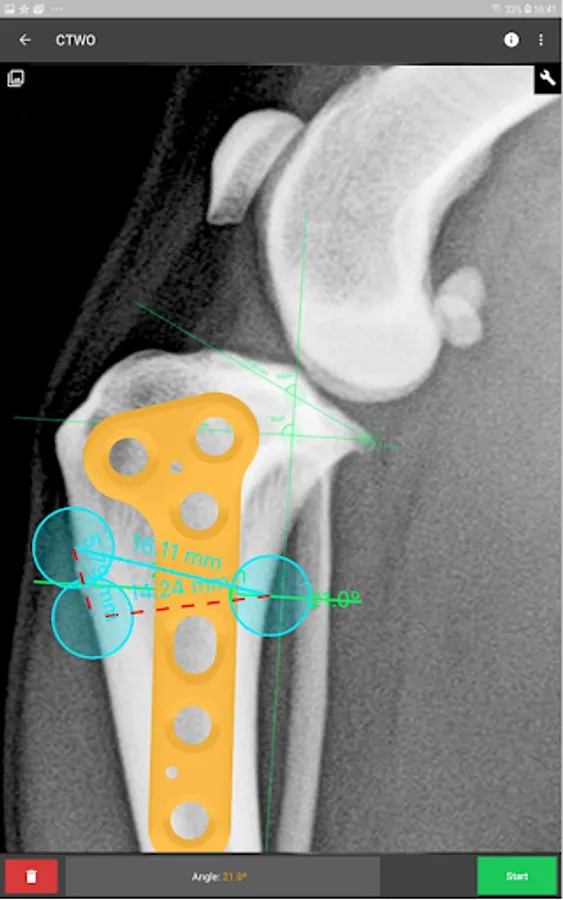

This is a useful tool for traumatology and orthopaedic surgical planning veterinary, including advanced techniques for treat canine anterior cruciate ligament (ACL) injuries (TPLO and CTWO).

3. Tools:

b) Radial measure/Circle draw.

c) Angle measure/Triangle draw.

e) Wedge cut, CTWO and angular osteotomies.

4. Catalogue of BETA Implants locking plates, in 2.0, 2.4, 2.7 and 3.5 sizes:

l) CTWO plates